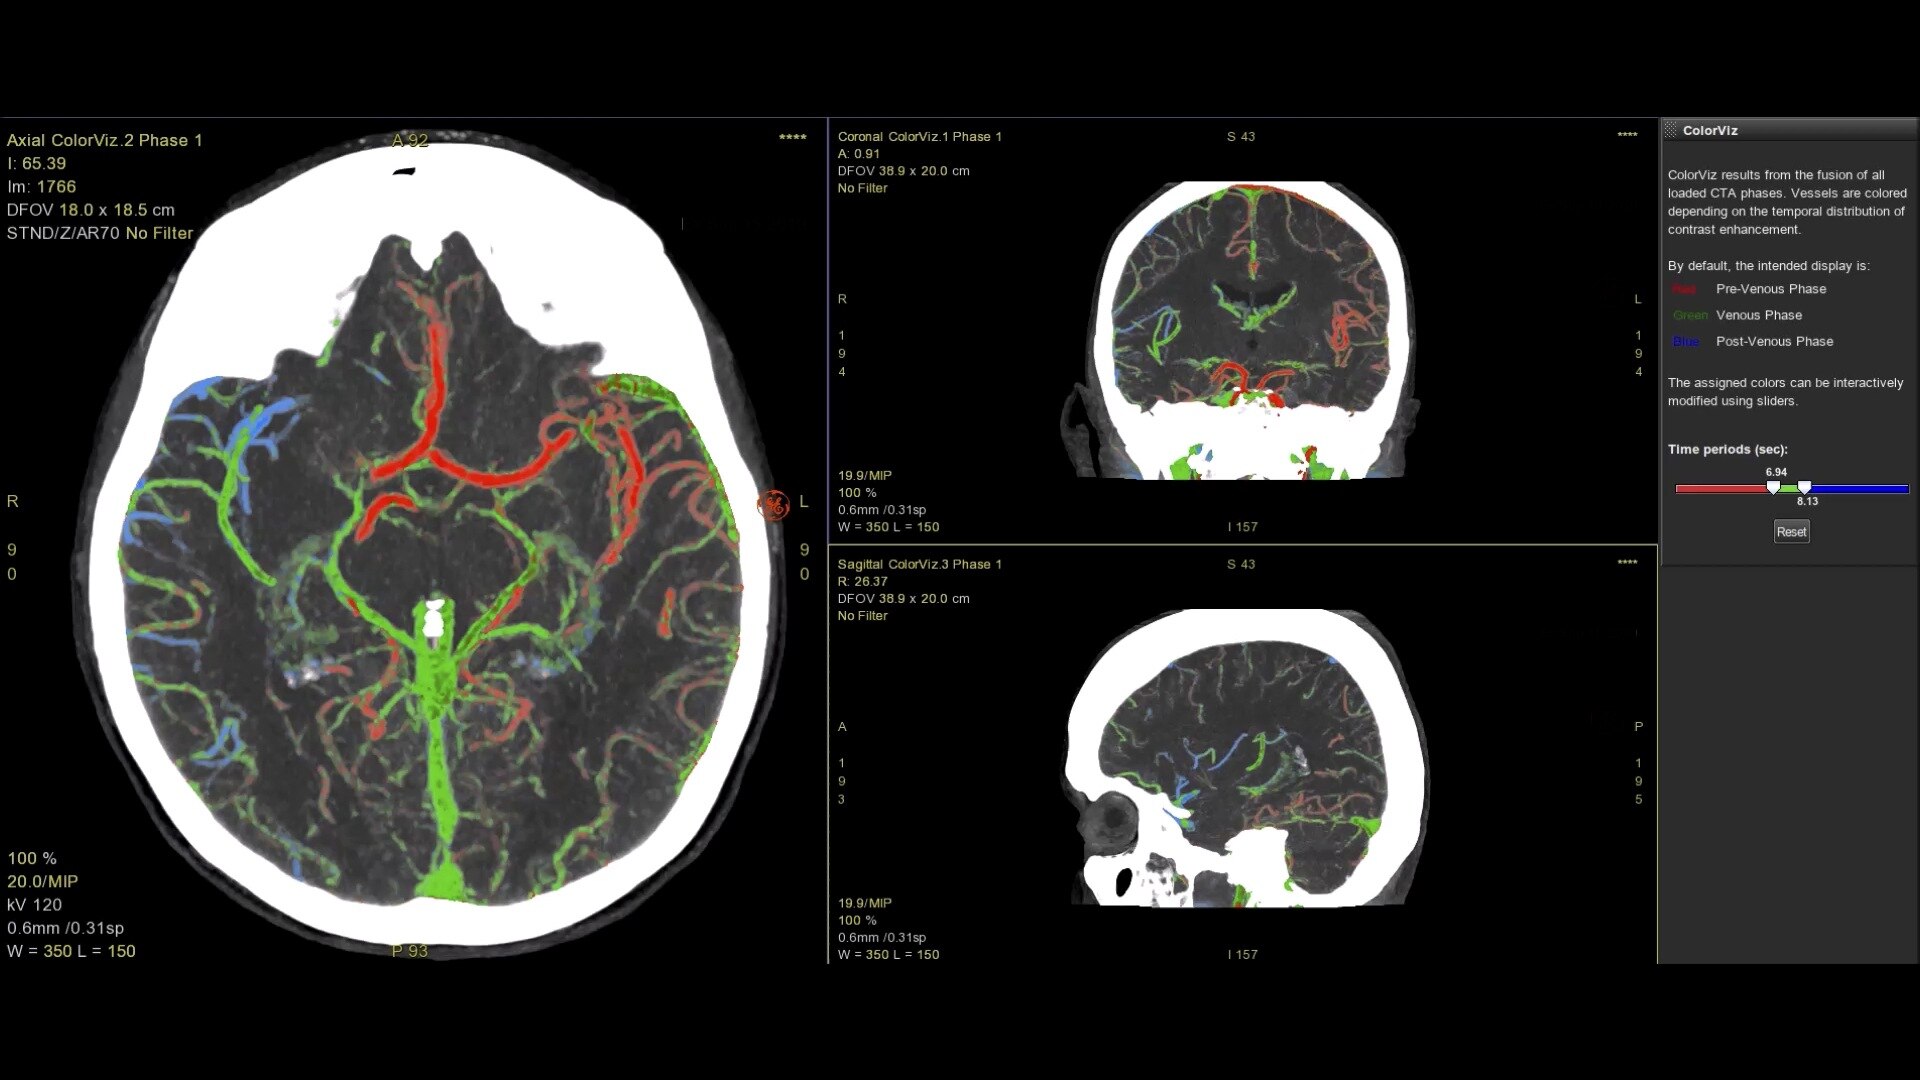

• ColorViz, an intelligent color-coded display enabling easy and confident identification of vascular enhancement timing

3-interactive-workflow-desktop